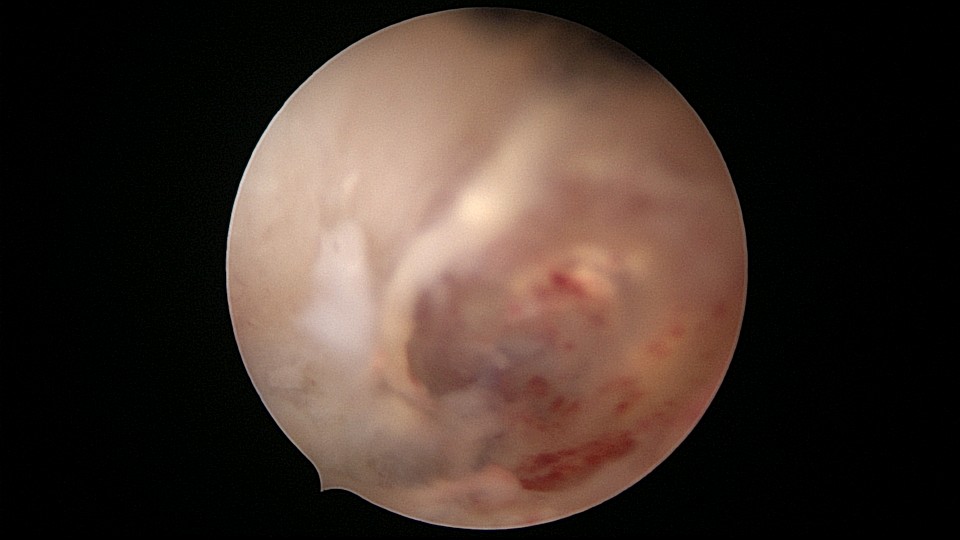

患者28岁,G7P3,顺产3次,完全纵膈子宫,单宫颈。2015年、2018年顺产,2019年左侧宫腔计划外妊娠行宫腔镜取胚及左侧宫腔放置γ环(推测既往妊娠左侧宫腔妊娠可能性大)。2023年4月带环受孕(应该为右侧宫腔妊娠),2023年12月足月阴道分娩,分娩时试图取出左侧宫腔内节育器,因操作困难,取环失败。2024年2月顺产后67天,要求取出宫内节育器,左手臂放置皮埋避孕棒。B超提示环距宫底1.1cm,环两翼分别距子宫前壁浆膜面0.4cm,距子宫后壁浆膜面0.3cm。宫腔镜术中膨宫困难,见宫颈管及宫腔少许淡黄色脓液流出,γ环逆时针旋转约80度,两臂指向左侧宫腔前后壁(2019年放置环时亦如此,因单侧宫腔前后径大于横径所致)。异物钳取出节育环,左右侧宫腔均见散在黄色机化组织,未取病检。